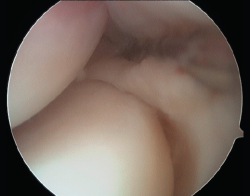

Baker et al.(29) describen 3 tipos de lesiones macroscópicas identificables mediante artroscopia exploradora de codo en los pacientes con epicondilitis (Figura 10):

- Tipo I: cápsula lisa sin irregularidades, inflamación y erosión en el tendón del músculo ECRB, sin muestras de desgarro completo.

- Tipo II: desgarros lineales o longitudinales en la cápsula por dentro de la superficie del origen del ECRB.

- Tipo III: lesión y retracción capsular con avulsión parcial o total del tendón del ECRB.

Aunque esta clasificación puede resultar útil a la hora de describir los cambios patológicos en la articulación, su valor pronóstico es limitado(30).

Figura 10. La clasificación de Baker de los hallazgos artroscópicos en la tendinopatía lateral del codo. A: tipo I, cápsula lisa sin irregularidades, inflamación y erosión en el tendón del músculo extensor carpi radialis brevis (ECRB), sin muestras de desgarro completo; B: tipo II, desgarros lineales o longitudinales en la cápsula por dentro de la superficie del origen del ECRB; C: tipo III, lesión y retracción capsular con avulsión parcial o total del tendón.